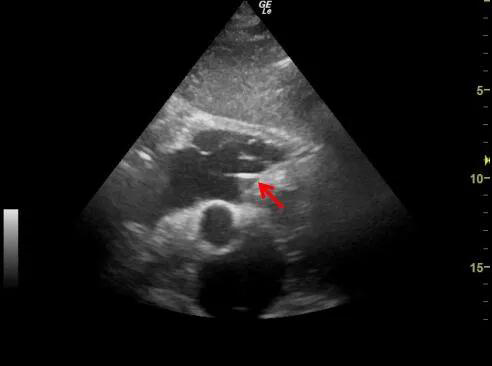

心脏超声图像,

红色箭头显示电极植入部位

手术植入以及超声定位电极位置